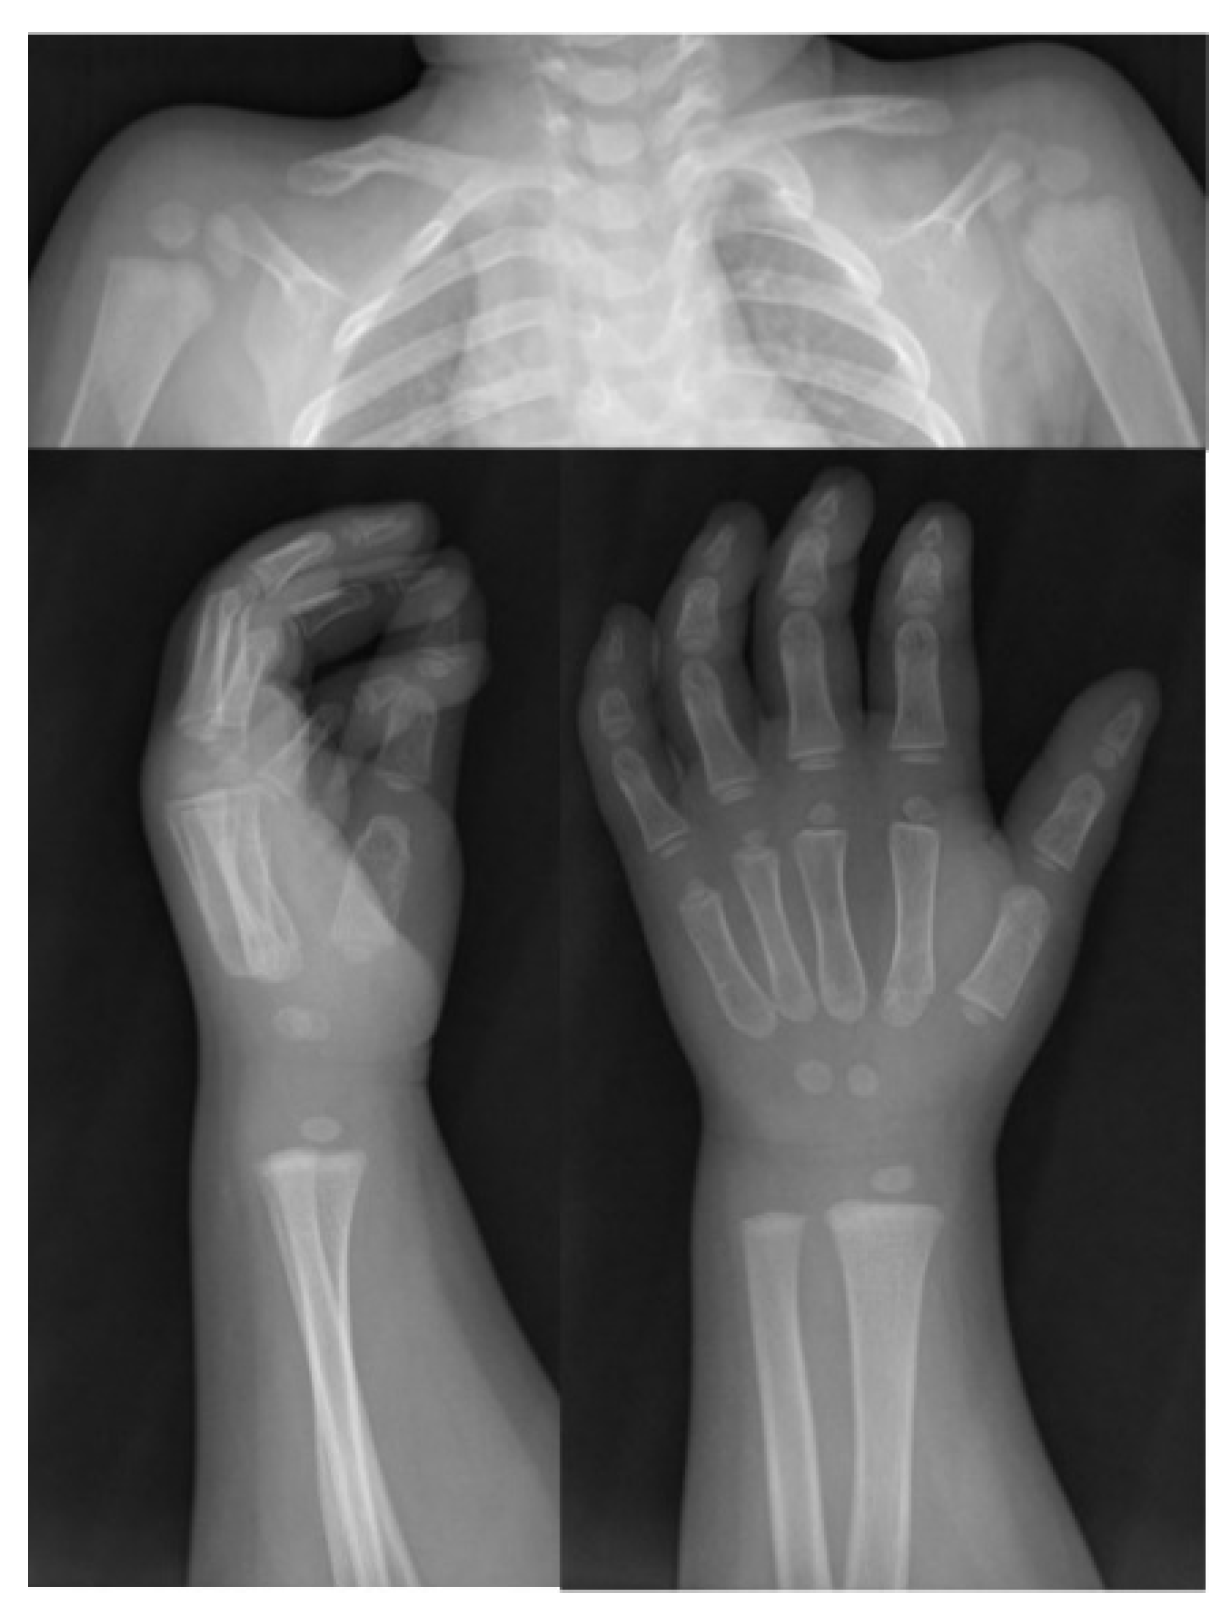

2.1. Clinical Data